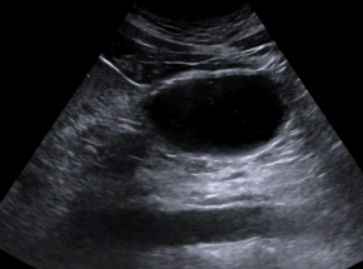

3. 应以最小压力将探头垂直放置于剑突下,平行于正中线,标记点朝向患者头侧(图1)。

图片

1  探头放置及体表定位图